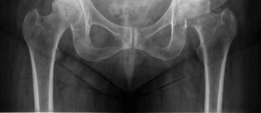

Standard antero-posterior and cross-table lateral radiographs of the pelvis and left hip were obtained immediately following the primary clinical assessment.

The initial AP pelvis radiograph clearly demonstrated a displaced left femoral neck fracture. The fracture line was entirely intracapsular. The femoral head was superiorly and posteriorly displaced relative to the femoral neck, with evidence of approximately 1.5 cm of shortening. The bone quality appeared reasonable for the patient's age, with a preserved Singh index and cortical thickness in the diaphyseal region, though some osteopenia was evident in the proximal trabecular patterns. No signs of pre-existing significant hip osteoarthritis (such as joint space narrowing, subchondral sclerosis, or osteophytosis) in the ipsilateral joint were noted. The contralateral hip appeared unremarkable.

Further radiographic views confirmed the complete displacement and the lack of cortical contact between the proximal and distal fragments. The fracture was classified as a Garden Type IV, indicating complete displacement with a loss of trabecular alignment between the femoral head and the acetabulum, where the head has rotated independently of the neck. Furthermore, it was classified as a Pauwels Type III, meaning the fracture line angle was greater than 70 degrees from the horizontal. This vertical fracture orientation indicates extremely high shear forces across the fracture site, portending a very poor prognosis for osteosynthesis and a high risk of nonunion or fixation failure if internal fixation were to be attempted.

Preoperative digital templating is a mandatory step in the surgical workflow for arthroplasty. Templating was performed on the AP pelvis radiograph, utilizing the contralateral, uninjured hip as a reference for restoring the center of rotation, femoral offset, and leg length. The templating process involves:

Given the patient's age and the presence of proximal femoral osteopenia (Dorr Type B/C bone morphology), templating was directed toward a hybrid total hip arthroplasty construct. This involves an uncemented, press-fit acetabular component and a cemented femoral stem. The templating confirmed that a standard offset cemented stem would adequately restore the patient's native biomechanics.